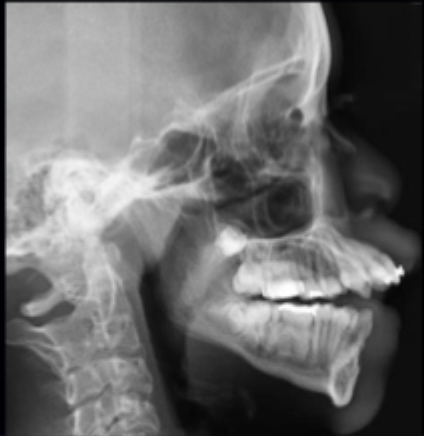

<p>what class of occlusion is shown in this x-ray? </p>

what class of occlusion is shown in this x-ray?

class II (x-ray)